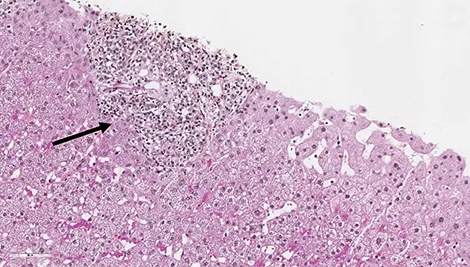

Les patients suivis pour une CBP peuvent présenter des degrés variables d’inflammation hépatique mais habituellement, dans la CBP, on retrouve très peu d’hépatite d’interface ou d’hépatite lobulaire. Environ 8 à 10 % des patients CBP vont présenter des lésions hépatiques faisant évoquer une HAI associée (1, 2). Le syndrome de chevauchement CBP+ HAI peut être présent d’emblée dès le diagnostic initial de la CBP dans 60 % des cas mais les patients CBP peuvent également, dans 30 % des cas, présenter une HAI dite secondaire apparaissant parfois plusieurs années après le diagnostic. Les patients HAI peuvent présenter dans 10 % des cas une CBP dite secondaire (figure 1) (3). Dans le cadre d’une CBP, une augmentation anormalement élevée des transaminases (> 5N) et des IgG (> 20 g/l) doit faire suspecter une HAI associée (4). Des anticorps anti- muscle lisse de spécificité anti-actine et des anticorps anti-ADN double-brin peuvent être présents dans 10 % des cas de CBP. Leur présence doit également faire suspecter l’existence d’un syndrome de chevauchement CBP+ HAI. Dans une étude s’intéressant aux anticorps anti-ADN double brin, ceux-ci étaient présents chez 60 % des patients CBP+ HAI, mais seulement chez 4 % des patients CBP et 26 % des patients HAI (p<0,0001 et 0,01 respectivement). La double positivité d’anticorps anti-ADN double brin et d’anticorps anti-mitochondries était présente chez 47 % des patients CBP+ HAI, mais seulement chez 2 % des pathologies contrôles (5). Dans une autre étude, la présence d’anticorps anti-ADN double brin, une augmentation des ALAT et des IgG étaient les trois facteurs significativement associés aux CBP+ HAI (6). De plus, chez les patients CBP non répondeurs à 12 mois à l’acide ursodésoxycholique (AUDC), une HAI doit être systématiquement recherchée. La présence d’un seul élément évocateur d’HAI n’est en revanche pas suffisant pour poser le diagnostic de syndrome de chevauchement. La réalisation d’une biopsie hépatique, en l’absence de contre-indication, est nécessaire pour confirmer le diagnostic de CBP+ HAI. La présence d’une hépatite d’interface et/ou d’une hépatite lobulaire, bien que non spécifiques, et son intensité permet de confirmer la présence d’une HAI. Le score histologique « modified HAI » (mHAI) développé par Ishak et al. permet de décrire l’activité hépatique inflammatoire et définit les indications de traitement (7, 8). Ce score décrit 4 catégories d’inflammation nécrotico-inflammatoire : l’hépatite d’interface périportale, la nécrose confluente, l’inflammation lobulaire et l’inflammation portale (figure 2). Un score mHAI> 4 est une indication de traitement immunosuppresseur. Les critères de Paris définis par Chazouillières et al. sont cependant les plus couramment utilisés et recommandés par la société européenne pour l’étude du foie (EASL) pour poser le diagnostic de syndrome de chevauchement CBP+ HAI. Ils reposent sur la présence d’au moins deux critères sur trois de CBP : PAL> 2N ou GGT> 5N ; anticorps anti mitochondries≥ 1/40 ; lésions biliaires florides à l’histologie et d’au moins deux critères sur trois d’HAI : ALAT> 5N ; IgG sériques> 2N ou présence d’anticorps anti muscle lisse ; une hépatite d’interface modérée à sévère en histologie (tableau 2, figure 2) (1). Dans une étude publiée en 2010, la sensibilité et la spécificité des critères de Paris pour diagnostiquer une CBP+ HAI étaient respectivement de 92 % et 97 % (9). Le score de Paris est un score différent de ceux utilisés pour faire le diagnostic de chaque pathologie propre CBP ou HAI. Le groupe de travail international de l’HAI ne recommande pas l’utilisation des scores diagnostiques habituels d’HAI (corrigés ou simplifiés) pour faire le diagnostic de CBP+ HAI du fait de leurs très faibles sensibilité et spécificité (9-12). L’objectif de poser un diagnostic de syndrome de chevauchement, et de manière précoce, est de pouvoir proposer un traitement adapté, notamment immunosuppresseur afin d’éviter la progression de la fibrose. Néanmoins, il est important de ne pas porter de diagnostic par excès afin d’éviter aux patients des effets secondaires d’une corticothérapie et/ou d’un traitement immunosuppresseur qui peuvent être sévères.

Figure 2 : Lésions histologiques biliaires évocatrices de CBP (A, B, C), lésions histologiques d’hépatite d’interface et d’hépatite lobulaire évocatrices d’HAI (D, E, F).